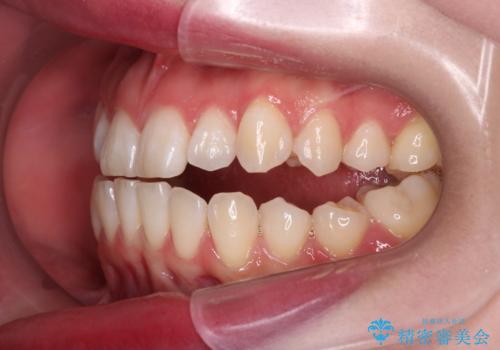

【ワイヤー矯正】一番後ろの奥歯でしか噛んでいないかみ合わせを治したい

最初は、一番後ろの奥歯でしか噛んでいない状態で、上下の前歯の先端がちょうど当たる切端咬合でした。

口腔習癖の改善及び、ワイヤー矯正にて歯列の平坦化を行うことで咬合を確立することができました。